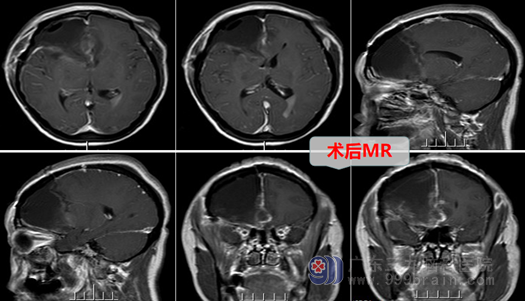

外十科主任欧阳辉教授热情地将她收住院。入院后欧阳主任结合磁共振、CTA等影像资料分析指出:患者右侧额颞岛叶占位性病变,病变范围广、是跨脑叶肿瘤,考虑成人弥漫性胶质瘤,应该尽快做手术。于是外十科团队很快为患者做好了术前准备,于第二天在全麻下行右侧额颞岛叶-胼胝体膝部-基底节区胶质瘤切除术。

术中见:肿瘤周边临近重要神经血管(大脑中动脉及其主要分支),部分血管甚至穿插在肿瘤中,这大大增加了手术的难度,因为医生不仅仅要切除肿瘤,还要保证不损伤重要神经血管,以免造成患者的功能损伤(对侧偏瘫)。这种既要兼顾肢体功能的保护,又要保证肿瘤的尽量切除,确实给医生带来了艰难的选择。欧阳教授主刀手术,在显微镜放大下,他如履薄冰、如临深渊,剑胆琴心,像雕刻家一样采取“雕刻式”手术,在重要血管间抽丝剥茧,尽最大耐心去切除肿瘤。

手术终于结束,在手术室门口,医生遇到焦急等待的患者家属,疲惫的医生告诉其家属:患者手术过程顺利,其家属激动地流下了感动的泪水。